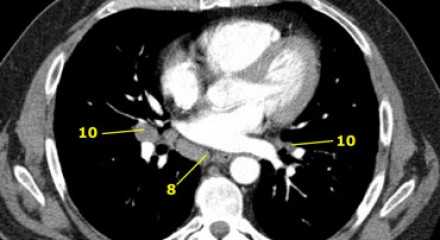

8. Параэзофагеальные лимфатические узлы

Эти лимфатические узлы ниже подкаринальных лимфатических узлов и распространяются каудальнее до диафрагмы. На изображении слева ниже уровня карины справа от пищевода обозначен лимфатический узел 8 группы.

10. лимфатические узлы корня легкого

Лимфатические узлы корня расположены проксимальнее долевых узлов, но дистальнее медиастинальной дупликатуры и узлов промежуточного бронха справа.

Все лимфатические узлы 10-14 групп являются N1 узлами, так как они находятся вне средостения.